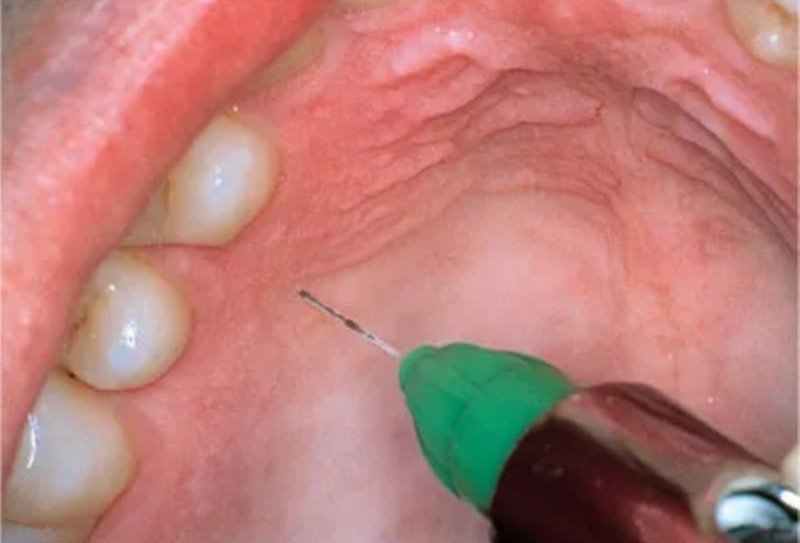

(+ 단단할 입천장은 마취약이 퍼지는 범위도 좁아서 필요하면 여러 번 찔러야 한다고)